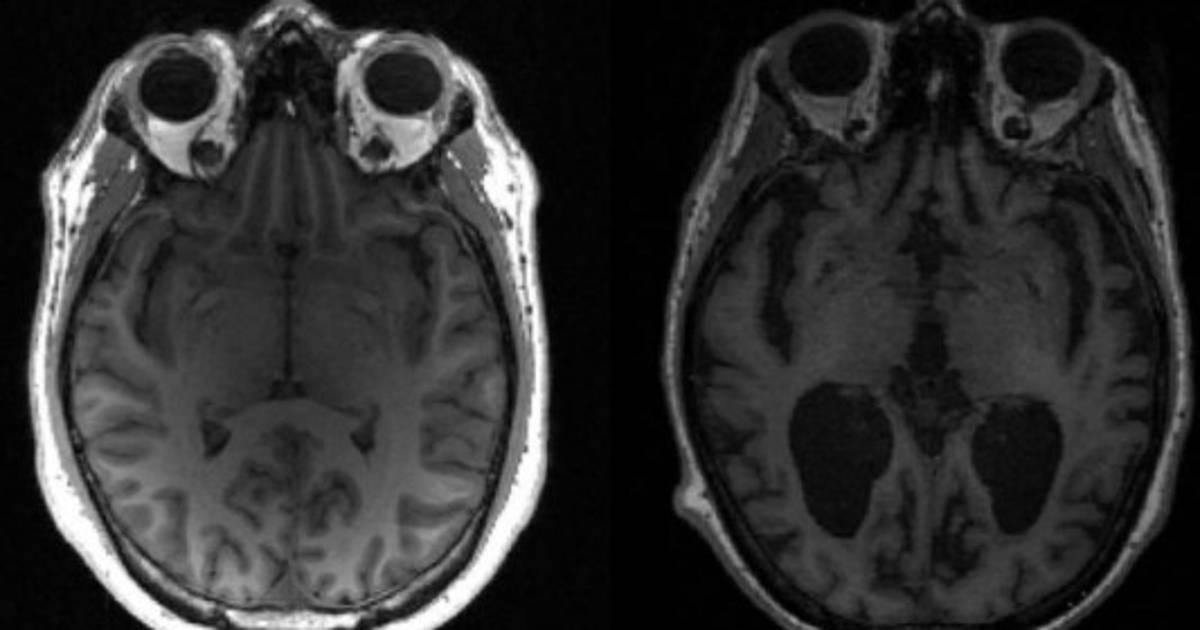

La esclerosis múltiple es una enfermedad autoinmune del sistema nervioso central (cerebro y médula espinal). Provoca un disfuncionamiento del sistema inmunitario, que ataca a la mielina, que protege las fibras nerviosas.

Evolucionando por etapas, la enfermedad es muy variable de un paciente a otro, pero puede conllevar secuelas, y es causa frecuente de discapacidad entre jóvenes adultos.